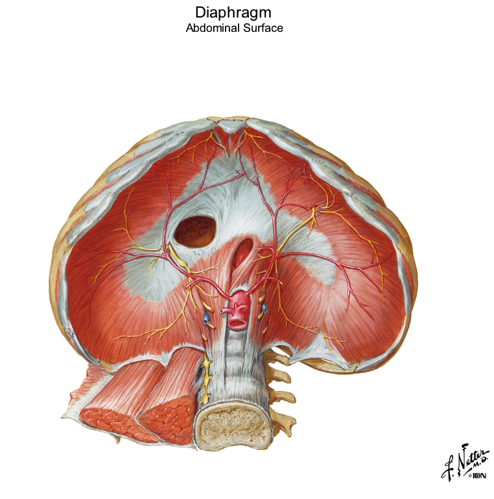

looking inside the diaphragm what can you see in the middle? what color is it? what does it serve as?

name the 3 openings of inside the diaphragm? point them out in picture

which hole opens through the central tendon?

central tendon

white

muscles all converge here on this central circle

central tendon is the upside down C

caval foramen is the big hole...opens up through the central tendon

esophageal hiatus is the oval oblong hole in center and inferior

aortic hiatus is the hole where you can even see part of the aorta coming through...most posterior of the 3 openings

what passes through these openings in the diaphragm?

Openings:

- Caval foramen...Inferior vena cava

- Esophageal hiatus...esophagus

- Aortic hiatus...Aorta

the sternal region of the diaphragm has attachments where?

the costal part has attachments where?

the lumbar part has attachments where?

Regions:

- Sternal part...attachments “along sternum”

- Costal part...attachments “along ribs”

- Lumbar part...attachments “along quadratus lumborum and psoas”

in picture: all regions form around the central tendon...small spot above is the sternal part...two huge kidney shapes on sides of central tendon are the costal regions...and the lumbar region is the space underneath the central tendon